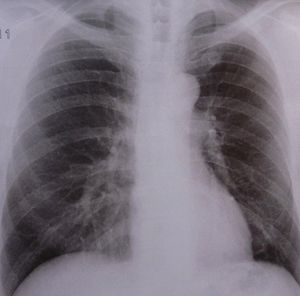

Lungen-Röntgen: Forscher rücken Tumoren zu Leibe (Foto: pixelio.de, D. Schütz) |